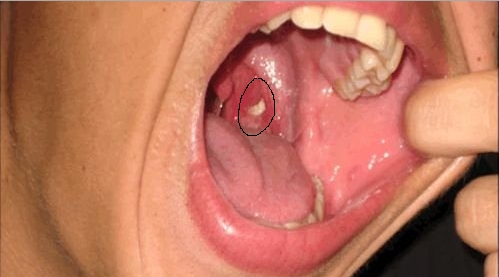

BELKİ İSMİNİ BİLE DUYMADINIZ AMA.. İŞTE AĞIZ KOKUSUNUN NEDENİ!

Bademciklerde çukur şeklinde kesecikler bulunur. Ağızdaki ölü mukaza hücreleri, burundan akan mukus bademcik taşlarını oluşturur.